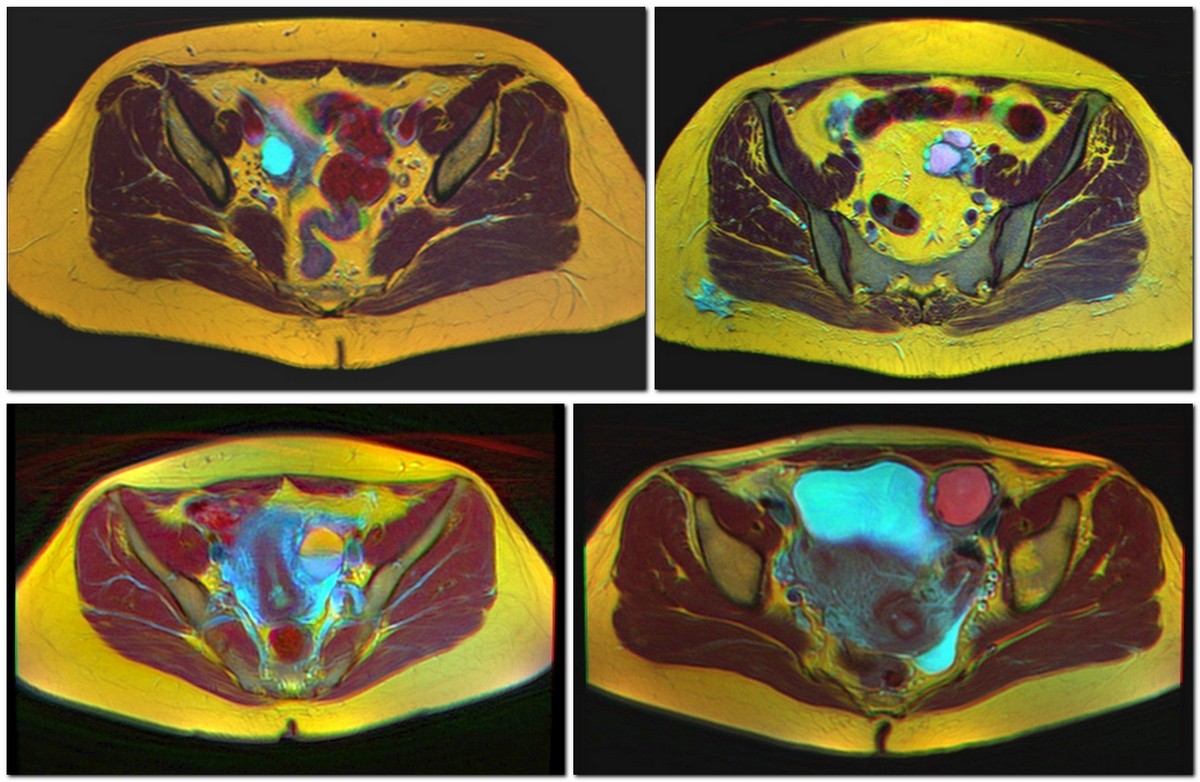

난소 낭종은 보통 초음파, CT 촬영, MRI 중 하나를 통해 진단한다.[13] 초음파는 가장 중요한 영상 기법인데, CT 촬영에서 이상 소견이 발견되더라도 초음파에서는 정상으로 나타나는 경우가 있기 때문이다.[4][6] 다른 영상 기법이 필요한 경우, MRI가 CT 촬영보다 더 신뢰할 수 있다.[4] 경험이 풍부한 초음파 검사자는 대개 양성 난소 낭종을 쉽게 식별할 수 있으며, 다른 접근 방식에 필적하는 정확도를 보이기도 한다.[4]

가임기 여성에서 우연히 발견된 단순 낭종은 5cm까지는 추적 영상 검사가 필요하지 않다. 이는 보통 정상적인 난포이기 때문이다. 폐경기 전 여성의 경우 5~7cm의 단순 낭종은 매년 추적 관찰해야 한다. 7cm보다 큰 단순 낭종은 MRI 또는 수술 평가가 필요하다. 낭종이 크기 때문에 초음파만으로는 신뢰성 있게 평가할 수 없기 때문이다. 이 크기와 깊이에서는 초음파 빔의 투과력이 제한되어 후벽 연조직의 결절이나 두꺼워진 중격을 확인하기 어려울 수 있다. 황체는 일반적으로 두꺼운 벽과 치상돌기가 있는 내부 경계를 가진 낭종으로 나타나는 우성 배란 난포인데, 직경이 3cm 미만이면 추적 관찰이 필요하지 않다.[6] 폐경기 후 여성의 경우, 1cm보다 크고 7cm 미만인 단순 낭종은 매년 추적 관찰이 필요하며, 7cm보다 큰 낭종은 가임기 여성과 유사하게 MRI 또는 수술 평가가 필요하다.[15]

우연히 발견된 기형종은 초음파에서 병적 징후인 에코성 지방으로 진단되며, 여성의 나이에 관계없이 수술 제거 또는 매년 추적 관찰이 권장된다. 복막 포함 낭종은 쭈글쭈글한 종이 모양을 보이며 인접 장기의 윤곽을 따르는 경향이 있으며, 추적 관찰은 임상 병력을 기준으로 한다. 수반증, 즉 나팔관 확장증은 무에코성으로 인해 난소 낭종으로 오인될 수 있는데, 이에 대한 추적 관찰 역시 임상적 증상을 기준으로 한다.[15]

3mm 미만의 얇은 중격을 가진 다방성 낭종의 경우, 수술적 평가가 권장된다. 다방성 낭종의 존재는 신생물을 시사하지만, 얇은 중격은 신생물이 양성임을 의미한다. 두꺼워진 중격, 결절, 컬러 도플러에서 혈관 흐름, 또는 여러 초음파 검사에서 성장하는 경우에는 암에 대한 우려 때문에 수술적 제거를 고려할 수 있다.[15] 어린 갑상선기능저하증 환자의 약 75%에서 다낭성 난소가 나타나며, 큰 난소 낭종과 높은 난소 종양 표지는 반 와이크-그룸바흐 증후군의 증상 중 하나이다.[18] 소아 및 청소년의 CA-125 표지는 악성 종양이 없어도 자주 상승할 수 있으므로 보존적 치료를 고려해야 한다.